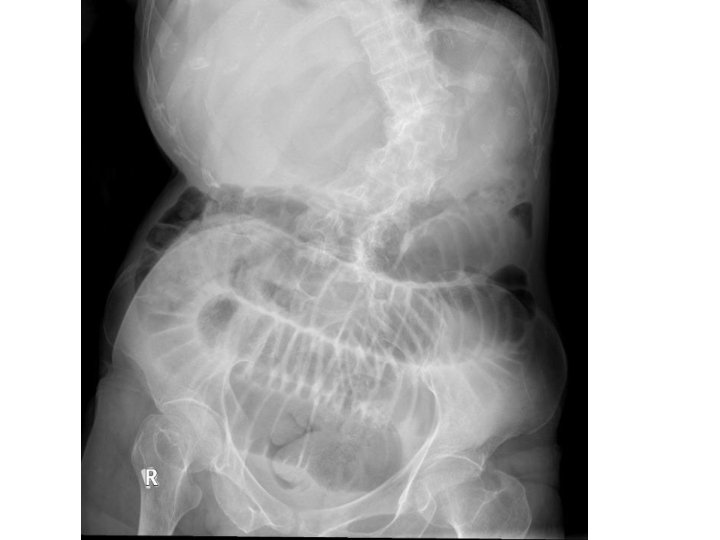

Case 5 • F/74 OAHR, Hx of CRHD, MS, CHF • Brought to AED for abdominal pain and repeated vomiting. • T 38. 4 C BP 93/60 P 127 Dehydrated • Abdomen: Mildly distended

What is the abnormality? (1 mark) • Dilated small bowel loops • No dilated large bowel noted, signifying small bowel obstruction

What are the initial management steps? (3 marks) • Patient should be kept nil by mouth • Ryle’s tube insertion to decompress the GI tract and reduce vomiting • Rehydration with IVF ◦ As she is dehydrated, running a low blood pressure and fever

What investigation would you perform? (1 mark) • CT abdomen and pelvis with contrast • In virgin abdomen, causes of SBIO are commonly ◦ hernia, extrinsic compression from peritoneal deposits, congenital adhesions (not likely for an old lady) ◦ luminal causes are FB, bezoar, food bolus (esp. for elderly) ◦ In the wall, there can be tumour at ICV, SB tumours are uncommon; strictures due to Crohn's disease are also possible • Otherwise, SBIO are commonly caused by adhesions • Don’t forget functional causes e. g. sepsis, electrolyte problems

What is the diagnosis? (1 mark) • Left obturator hernia causing small bowel obstruction

What are the risk factors? (2 marks) • Elderly female • Thin body build/recent weight loss • Notes ◦ Obturator hernias are a rare type of hernia. They are more commonly right sided, but can be bilateral. ◦ Women with wider obturator foramen is at risk. ◦ Risk is higher in elderly, malnourished ladies and in the setting of weight loss as the peritoneal fat is loss. ◦ The hernia sac usually contains SB, but LB, omentum, appendix or fallopian tube, omentum is possible. ◦ The diagnosis is usually made on CT scan or intraoperatively.

What is the classical sign for this condition? (1 mark) • Howship-Romberg sign • It is pain over medial thigh aggravated by hip extension, abduction and internal rotation • Notes ◦ Clinically, it can present as obturator neuralgia (groin pain radiating medially to the knee) compression of the obturator nerve ◦ Rarely there may be palpable proximal thigh mass (confused with femoral hernias), or ecchymosis of the thigh if bowel necrosis has occurred